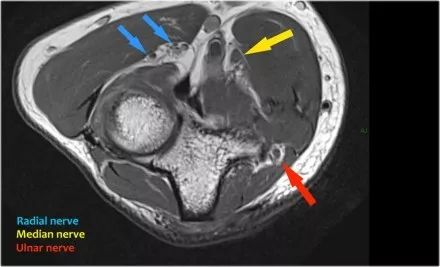

桡神经:在桡骨头水平可以最好地识别桡神经,在那里你可以看到桡骨隧道中的浅表和深支(箭头)。这是寻找桡神经的非常一致的地方。

深分支形成后骨间神经,穿过Frohse拱门(箭头)的旋后肌。

中位神经:正中神经落后于Lacertus纤维,即肱二头肌的腱膜并穿透旋前肌。